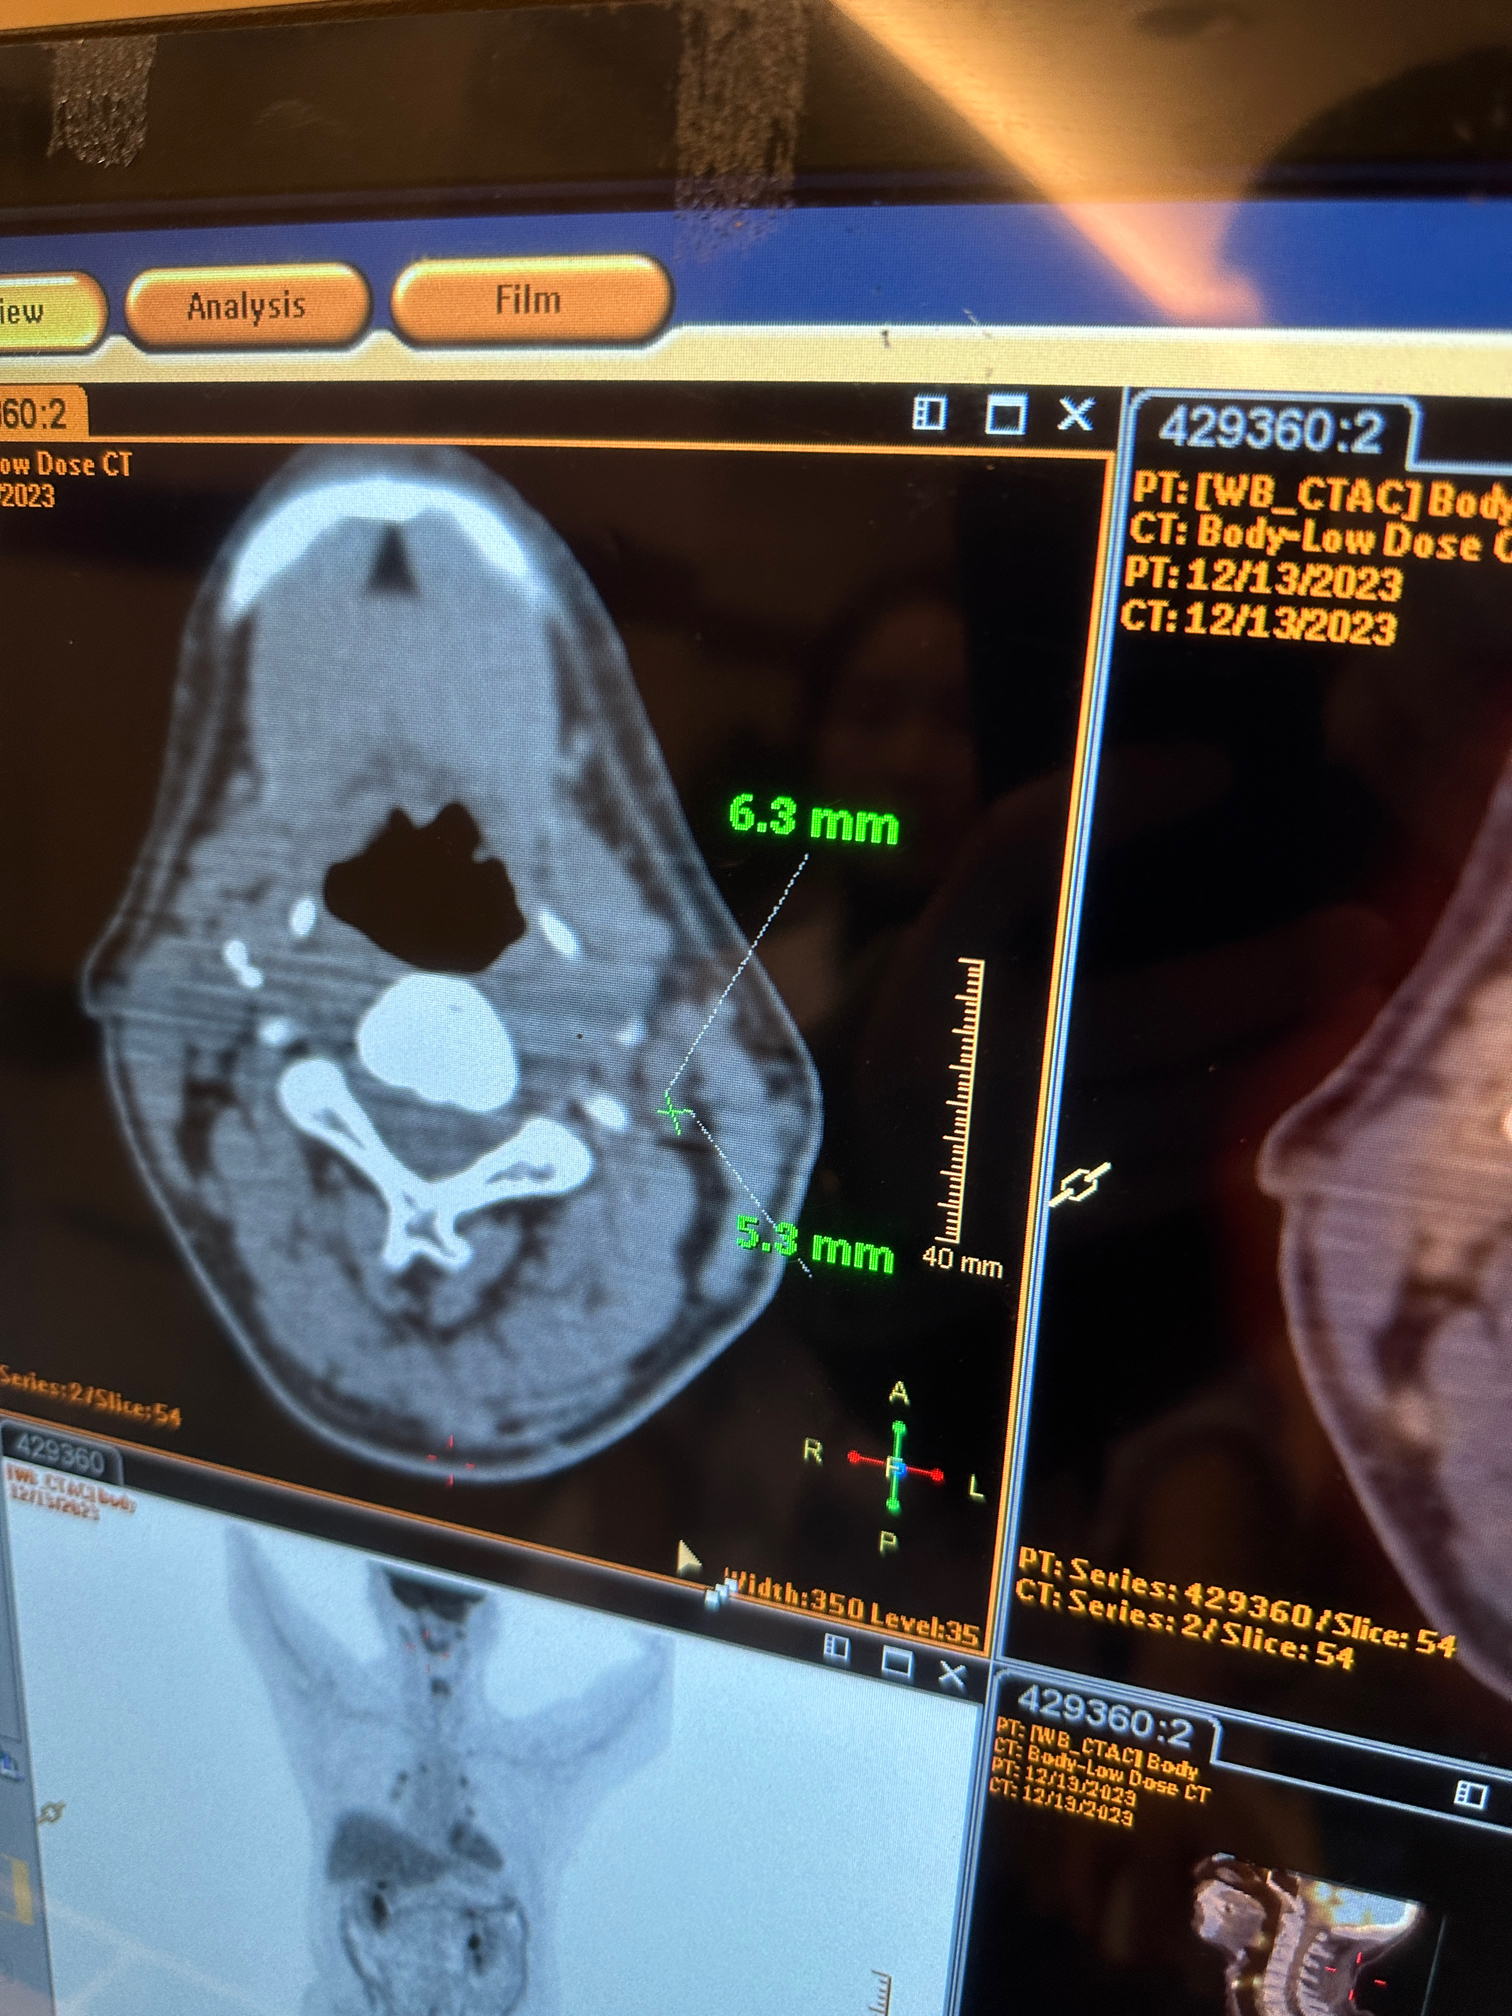

这个大小

看起就是圆形

尺寸太小没法活检

太小啦, 可以先观察  这个尺寸本身问题不大